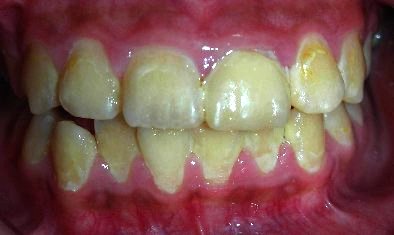

審美牙科 – 前牙美觀評估分

審美牙科

全瓷冠